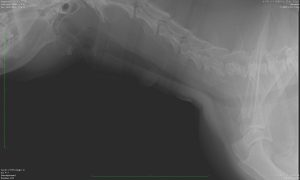

犬の頸部気管虚脱

胸部レントゲン検査では、頸部を中心に虚脱した気管が認められました。

(虚脱し、細くなった気管)